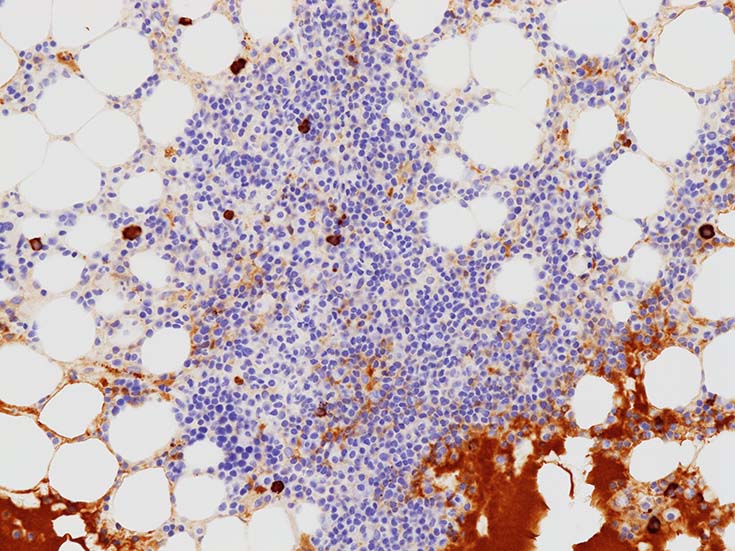

CD138陽性形質細胞の分布. 中央部よりも周辺部に陽性細胞が多くみられる.